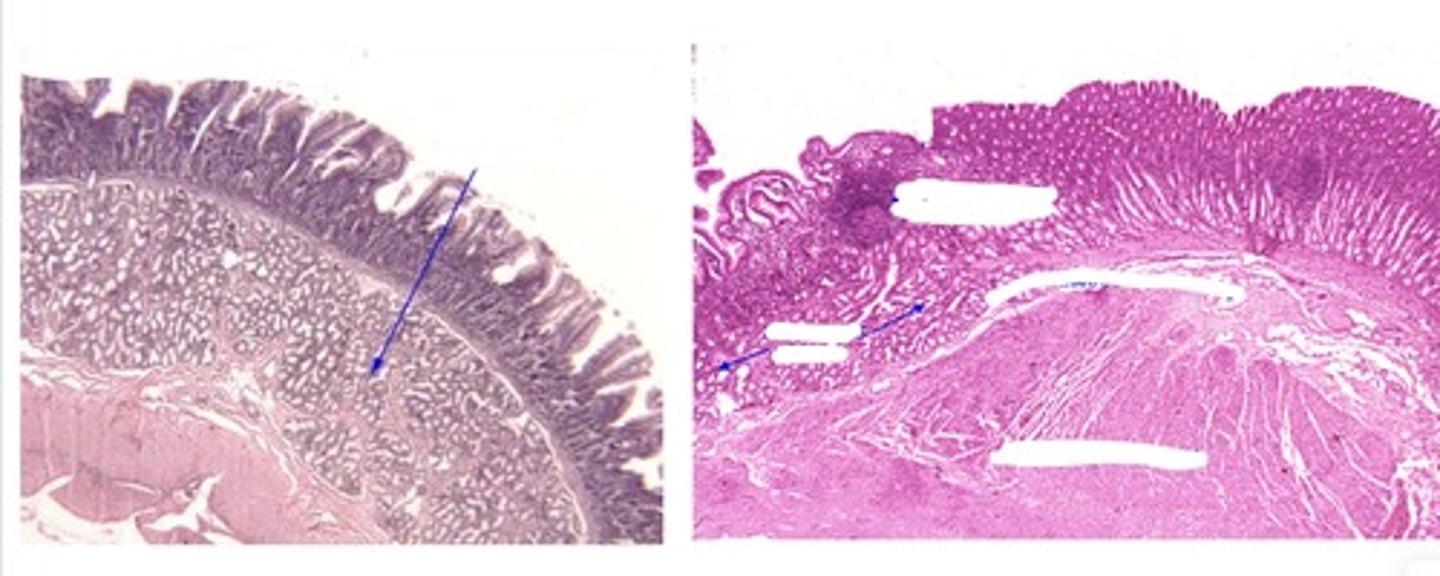

esophagus-stomach junction

Transition from strat squam to simple columnar epithelium

rectal-anal junction (rectum left anal right)